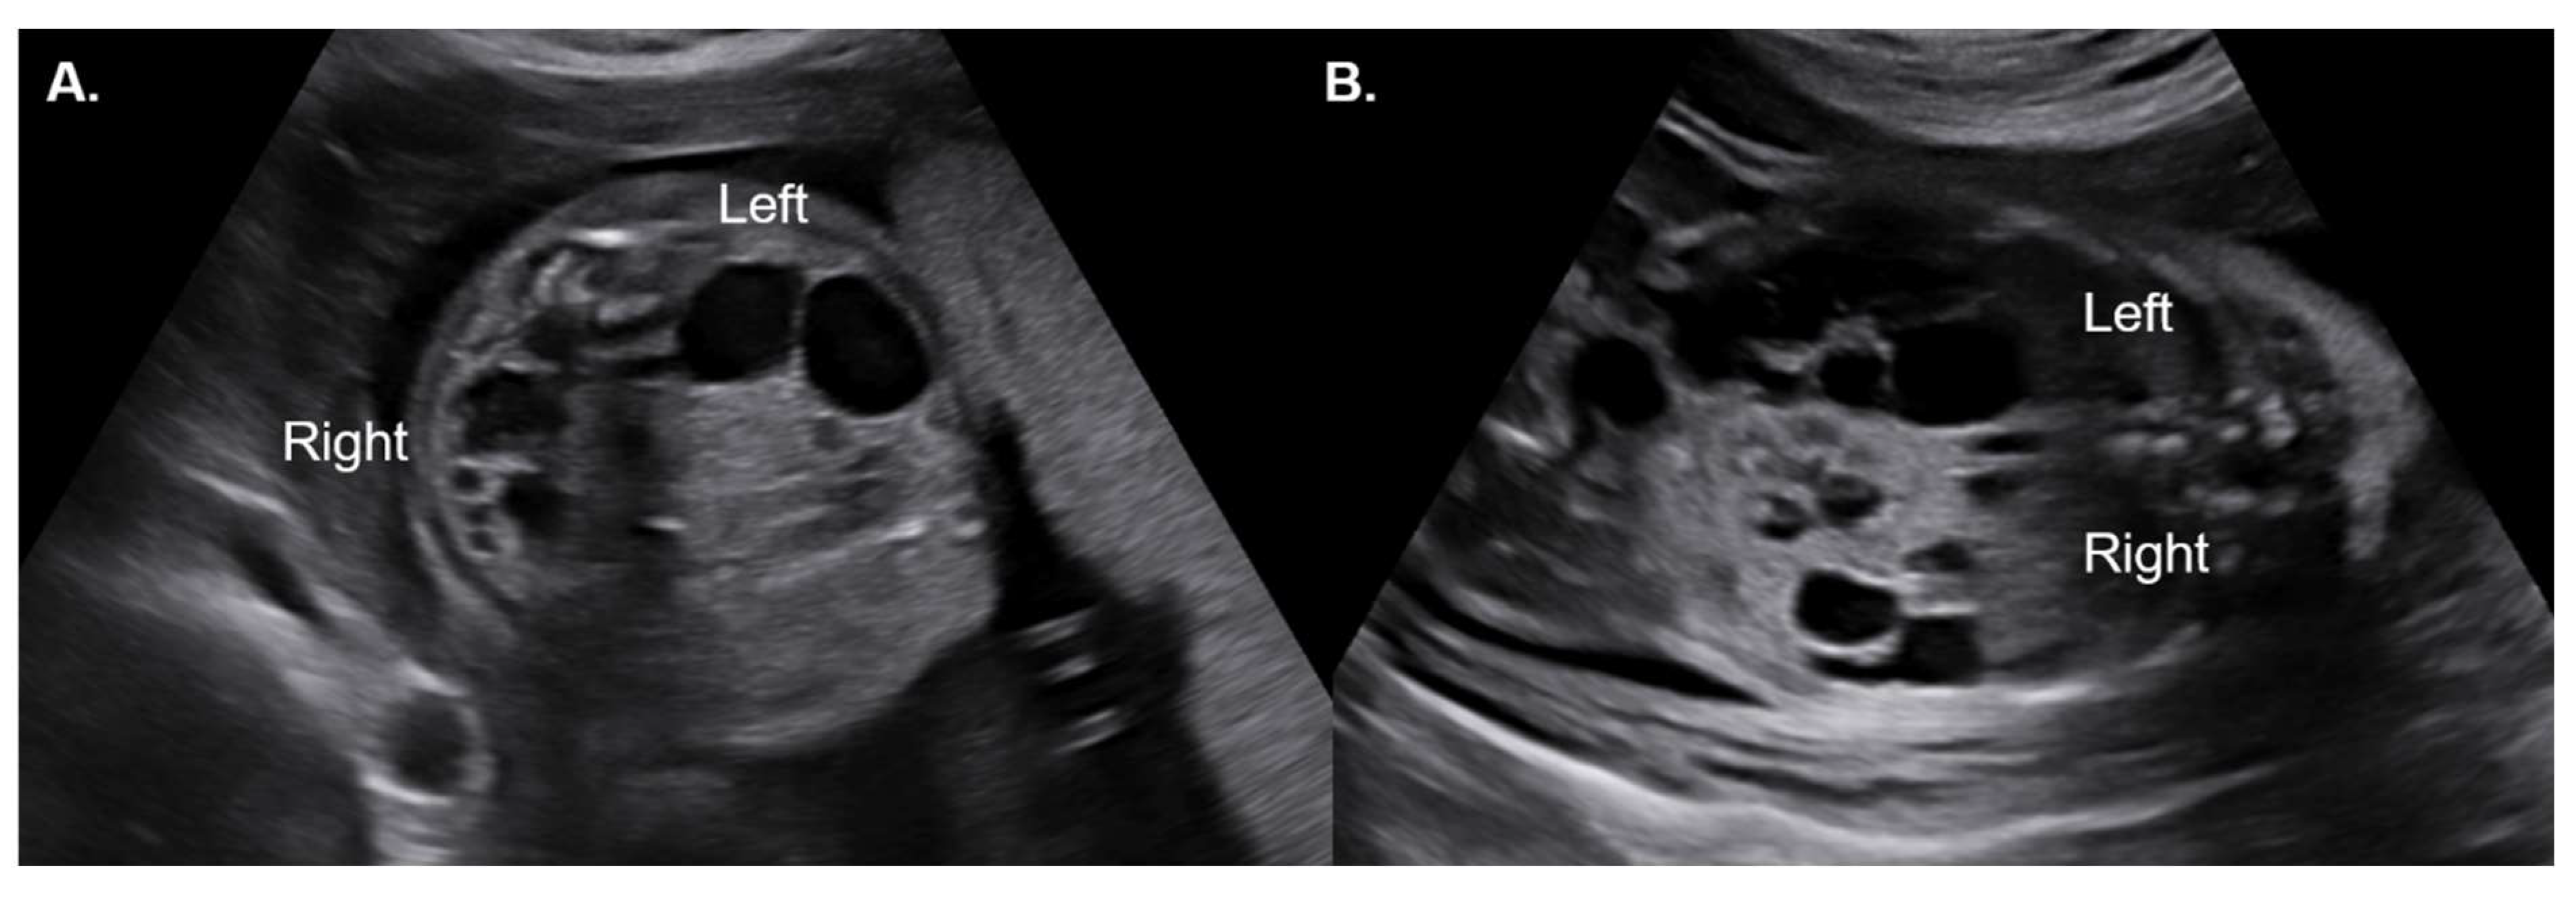

- Brun, M.; Maugey-Laulom, B.; Eurin, D.; Didier, F.; Avni, E.F. Prenatal sonographic patterns in autosomal dominant polycystic kidney disease: A multicenter study. Ultrasound Obstet. Gynecol. 2004, 24, 55–61. [Google Scholar] [CrossRef]

- Garel, J.; Lefebvre, M.; Cassart, M.; Della Valle, V.; Guilbaud, L.; Jouannic, J.M.; Ducou le Pointe, H.; Blondiaux, E.; Garel, C. Prenatal ultrasonography of autosomal dominant polycystic kidney disease mimicking recessive type: Case series. Pediatr. Radiol. 2019, 49, 906–912. [Google Scholar] [CrossRef]

- Gupta, A.; Aneja, A.; Bahl, N.; Arora, R.; Nadir, L.; Saini, P. Corticomedullary differentiation in fetal kidneys: A necessary evil? J. Fetal Med. 2024, 11, 139–144. [Google Scholar] [CrossRef]

- Buffin-Meyer, B.; Klein, J.; Aziza, J.; Fernandez, M.; Feuillet, G.; Seye, M.; Buléon, M.; Fédou, C.; Camus, M.; Burlet-Schiltz, O.; et al. Improved prenatal assessment of kidney disease using multiple ultrasound features. Nephrol. Dial. Transplant. 2025, 40, 341–351. [Google Scholar] [CrossRef]

| Increased cortical echogenicity | 17 (85.0%) |

| CMD | |

| Increased CMD | 15 (75.0%) |

| Reverse CMD | 1 (5.0%) |

| Loss of CMD | 2 (10.0%) |

| Presence of cortical cysts | 9 (45.0%) |